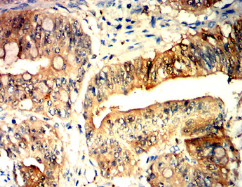

IHC    1/200 - 1/1000